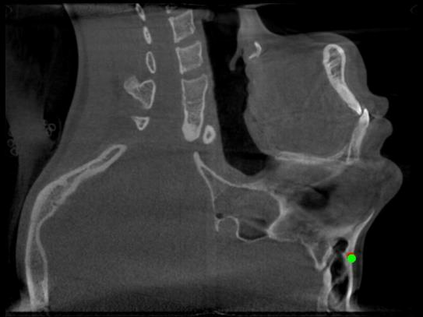

Detecting 3D landmarks on cone-beam computed tomography (CBCT) is crucial to assessing and quantifying the anatomical abnormalities in 3D cephalometric analysis. However, the current methods are time-consuming and suffer from large biases in landmark localization, leading to unreliable diagnosis results. In this work, we propose a novel Structure-Aware Long Short-Term Memory framework (SA-LSTM) for efficient and accurate 3D landmark detection. To reduce the computational burden, SA-LSTM is designed in two stages. It first locates the coarse landmarks via heatmap regression on a down-sampled CBCT volume and then progressively refines landmarks by attentive offset regression using multi-resolution cropped patches. To boost accuracy, SA-LSTM captures global-local dependence among the cropping patches via self-attention. Specifically, a novel graph attention module implicitly encodes the landmark's global structure to rationalize the predicted position. Moreover, a novel attention-gated module recursively filters irrelevant local features and maintains high-confident local predictions for aggregating the final result. Experiments conducted on an in-house dataset and a public dataset show that our method outperforms state-of-the-art methods, achieving 1.64 mm and 2.37 mm average errors, respectively. Furthermore, our method is very efficient, taking only 0.5 seconds for inferring the whole CBCT volume of resolution 768$\times$768$\times$576.